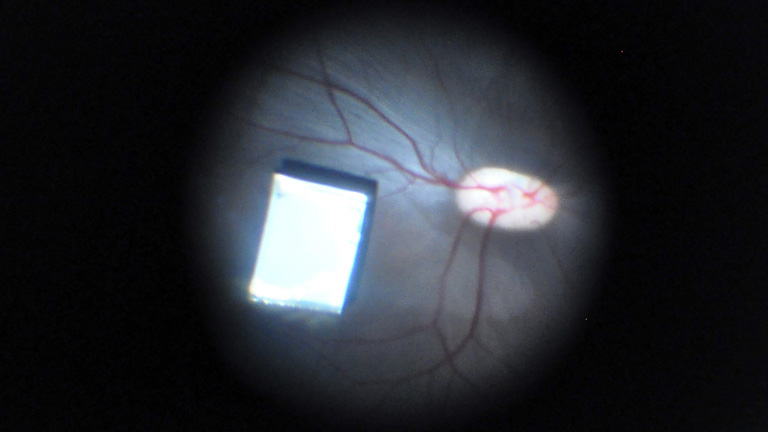

Científicos israelíes desarrollan una nano retina, un chip que devuelve parcialmente la vista

Tiene un tamaño similar al de un grano de arroz. La nano retina se implanta en el ojo en apenas treinta minutos y transmite señales visuales a...